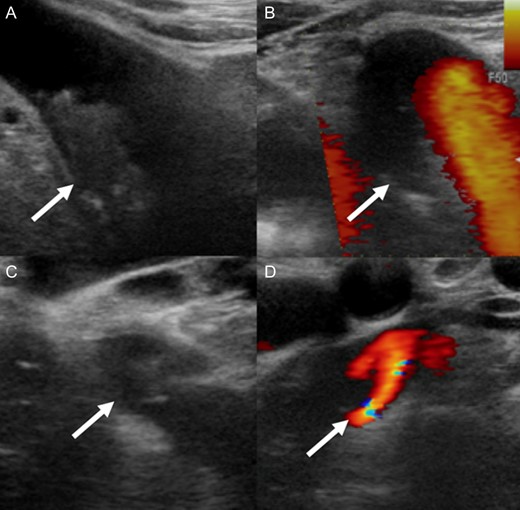

After admission, carotid ultrasonography revealed a large, soft plaque with ulceration in the IA and a very mobile soft plaque in the LSA (Fig. 3). EVT was thus considered too dangerous, and TAR using a four-branched prosthesis was planned. Intraoperatively, bilateral axillary arteries were initially exposed, and an 8-mm vessel prosthesis was anastomosed. Median sternotomy was then performed. Cardiopulmonary bypass was established with arterial perfusion via bilateral axillary arteries and bicaval venous drainage. TAR was performed under hypothermic circulatory arrest with antegrade selective cerebral perfusion, then the brachiocephalic artery and LSA were clamped and the left common carotid artery (LCA) was intubated. To avoid hoarseness due to injury of the left recurrent laryngeal nerve, a hybrid prosthesis (FROZENIX, Japan Lifeline, Tokyo, Japan) was used and a distal anastomosis was created between the LCA and LSA. The LCA was ligated and the prosthesis, which was anastomosed to the left axillary artery, was brought into the mediastinum and anastomosed with a branch of the four-branched prosthesis (Fig. 4). The postoperative course was uneventful and the patient was discharged on postoperative day 16 (Fig. 5).

A soft plaque with ulceration in the IA (A, B) and a very mobile soft plaque in the LSA (C, D).